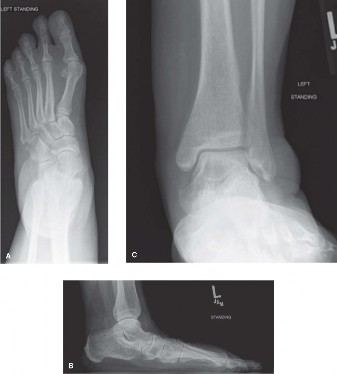

A 59-year-old female with a longstanding history of bilateral foot pain presents with a recurrent painful cal…